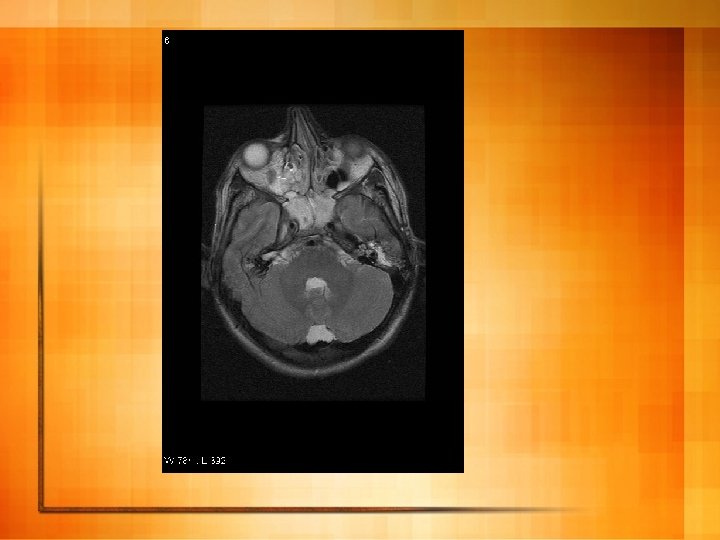

Case 1 l After d/w ID started on iv aciclovir and benzylpenicillin l 2 days later HSV PCR on CSF positive l MRI brain:

HSV encephalitis